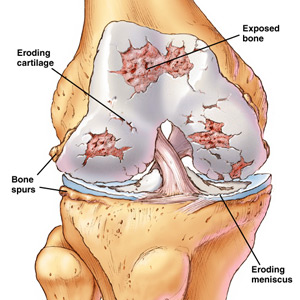

Let's clear up a misconception right from the start of this feature and one we strongly believe in. There is no question people with lower extremity problems, from the hips down to the toes can be a result of a multitude of causes. Injuries for one, old age reasons for another as in arthritis, cartilage erosion as described above and to the left. There are the bone spurs, meniscus issues, repetitive activity concentrating in one area, creating an imbalance, muscles in particular and of course dietary considerations including the right alkaline liquids to drink to flush out the wastes that accompany all of these problems. If you don't drink enough of the right liquids and we will cover this below, just get ready to eventually schedule a knee replacement leading to a hip job as well. It is inevitable and blood clots and staph infections could hop aboard for the ride.

A couple of examples would be muscle break down in the quadriceps, hamstrings

area. Those doogiggers illustrated on your right top and bottom attached and

wrapped over your knees are not there for cosmetic purposes. The